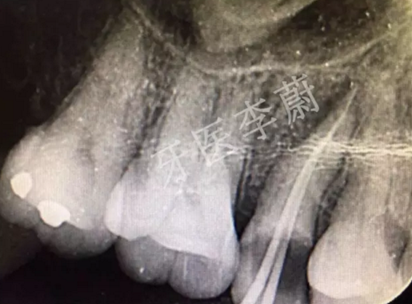

15牙根管預(yù)備試尖片